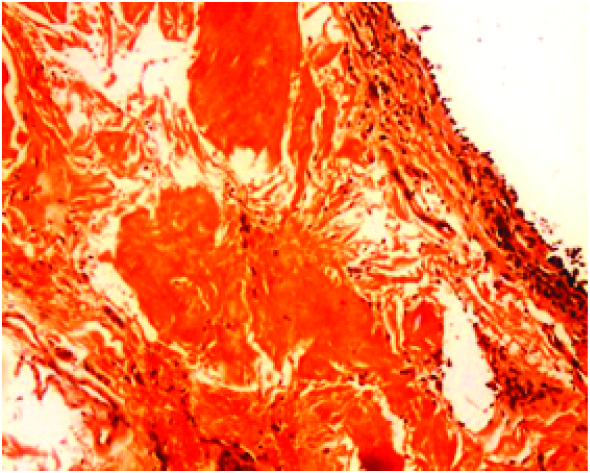

Transbronchial lung biopsy was done and showed subepithelial deposits of acellular eosinophilic homogenous material resembling amyloid [Table/Fig-3]. Some of these deposits formed casts surrounded by inflammatory cells composed of lymphocytes, histiocytes and multinucleate giant cells [Table/Fig-4].These deposits showed apple green birefringent under polarising microscopy using Congo red stain [Table/Fig-5]. Thioflavine T stained the deposits. On immunohistochemistry Lambda light chain antibody intensely stained the deposits [Table/Fig-6]. Kappa light chain antibody was negative.

Transbronchial lung biopsy was done and showed subepithelial deposits of acellular eosinophilic homogenous material resembling amyloid [Table/Fig-9]. These deposits showed apple green birefringent under polarising microscopy using Congo red stain [Table/Fig-10]. Thioflavine T stained the deposits. On immunohistochemistry Lambda and kappa light chain antibodies were negative. In addition there were foci of calcification.